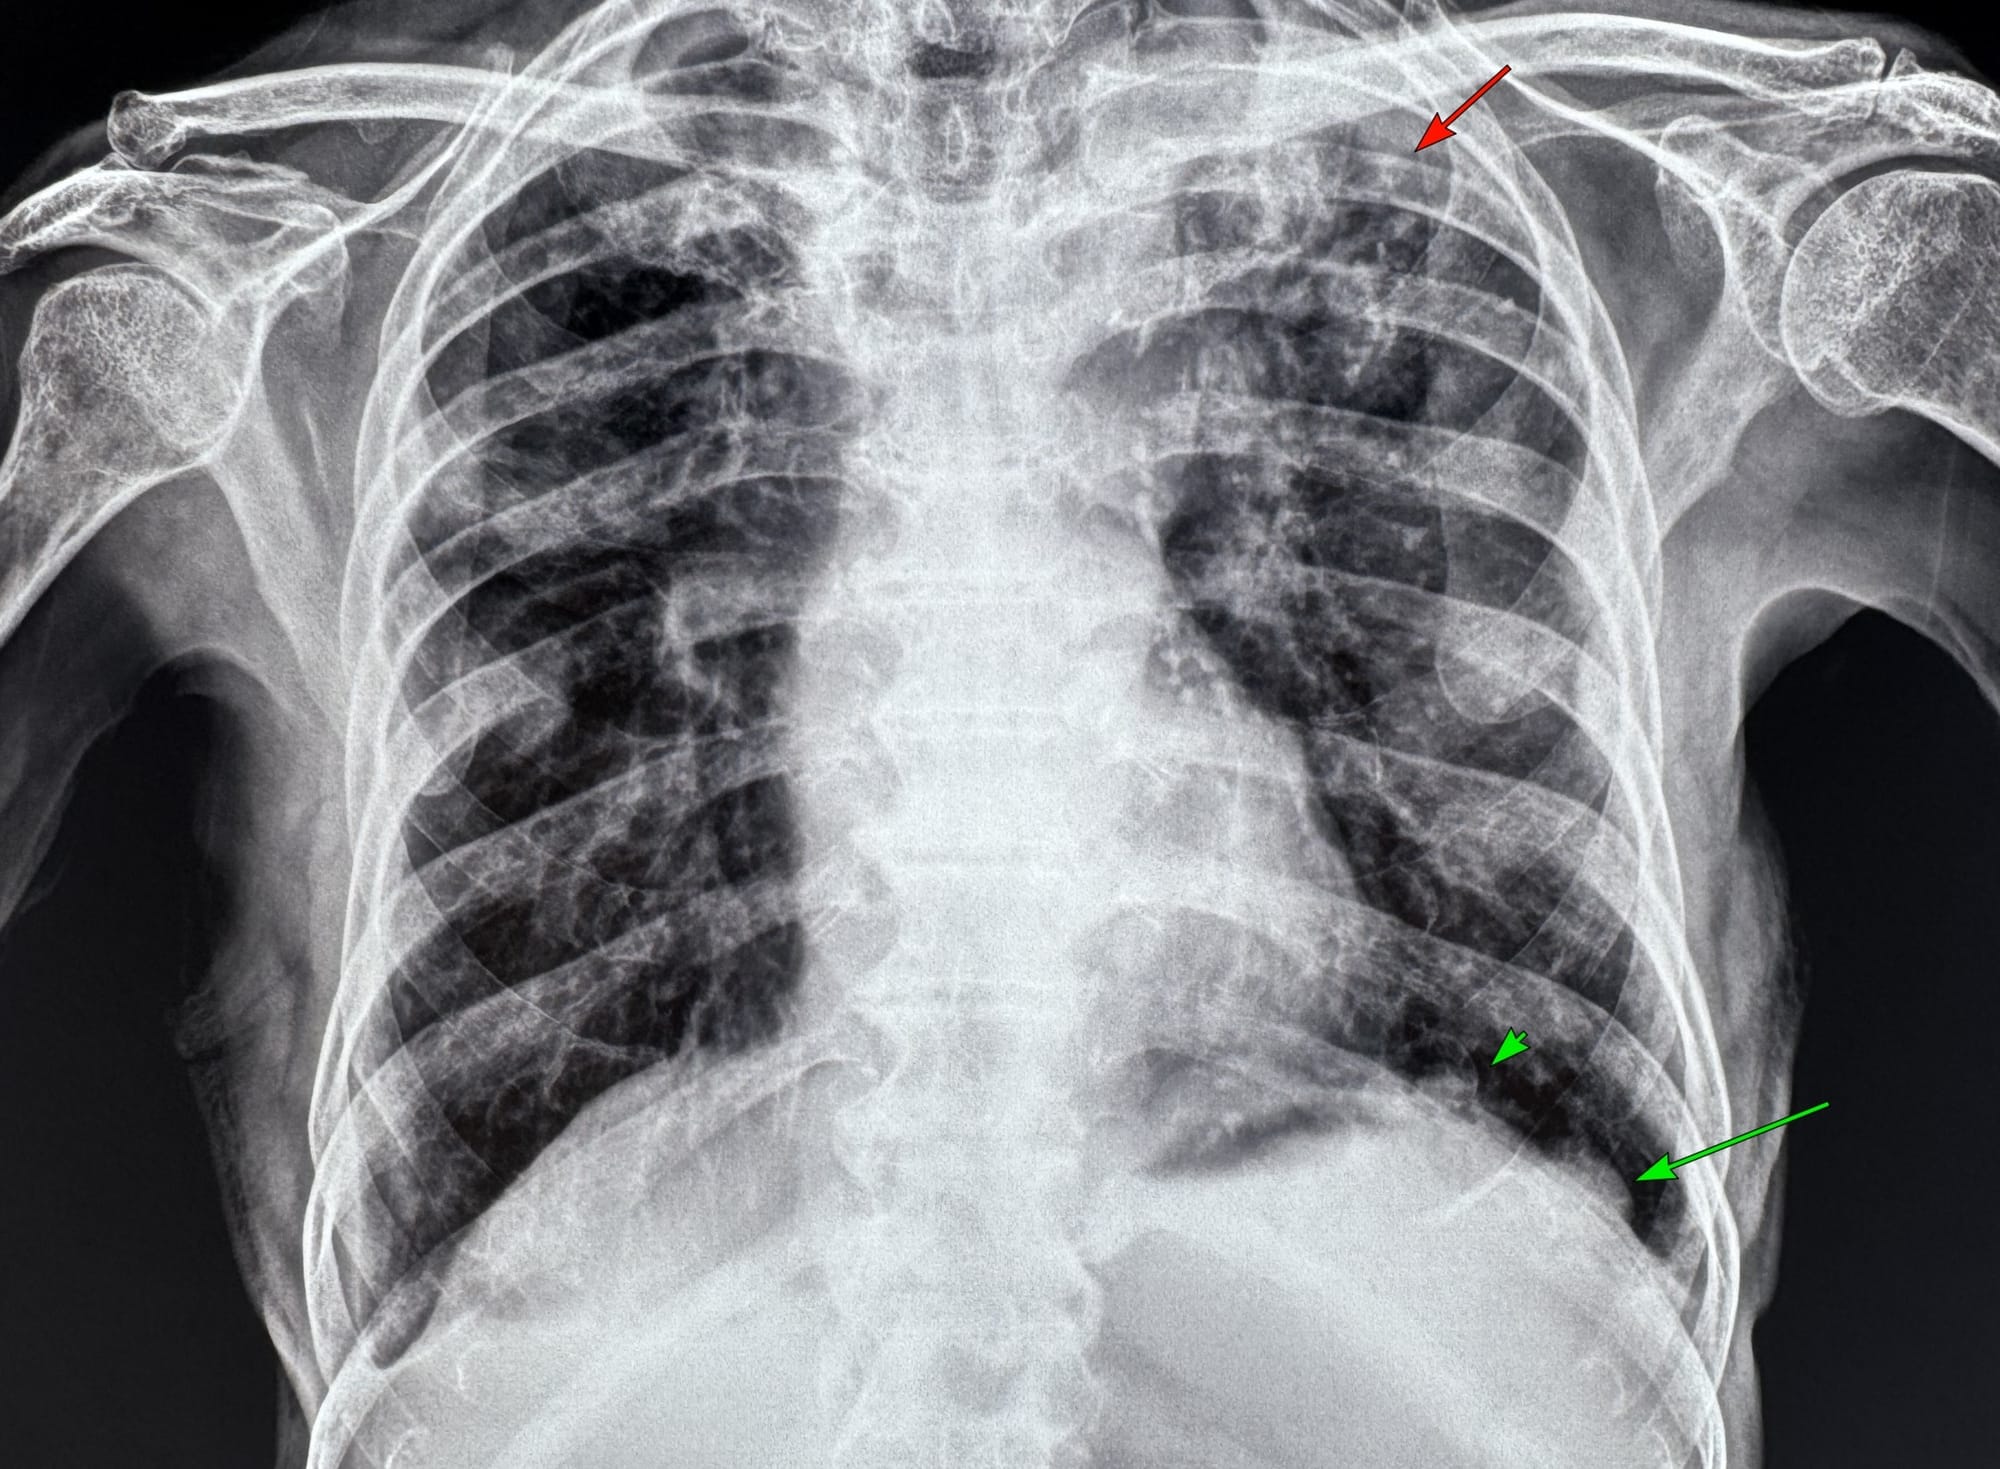

77-year-old man presented for an opinion with pleural plaques (green arrows) and upper lobe fibronodular lesions (red arrow) on a radiograph

The CT scan showed extensive pleural plaques (arrows), some calcified, some not.

He also had coexistent resolving tuberculosis (on AKT) with fibrocystic and fibrocavitary lesions in the upper lobes (arrows).